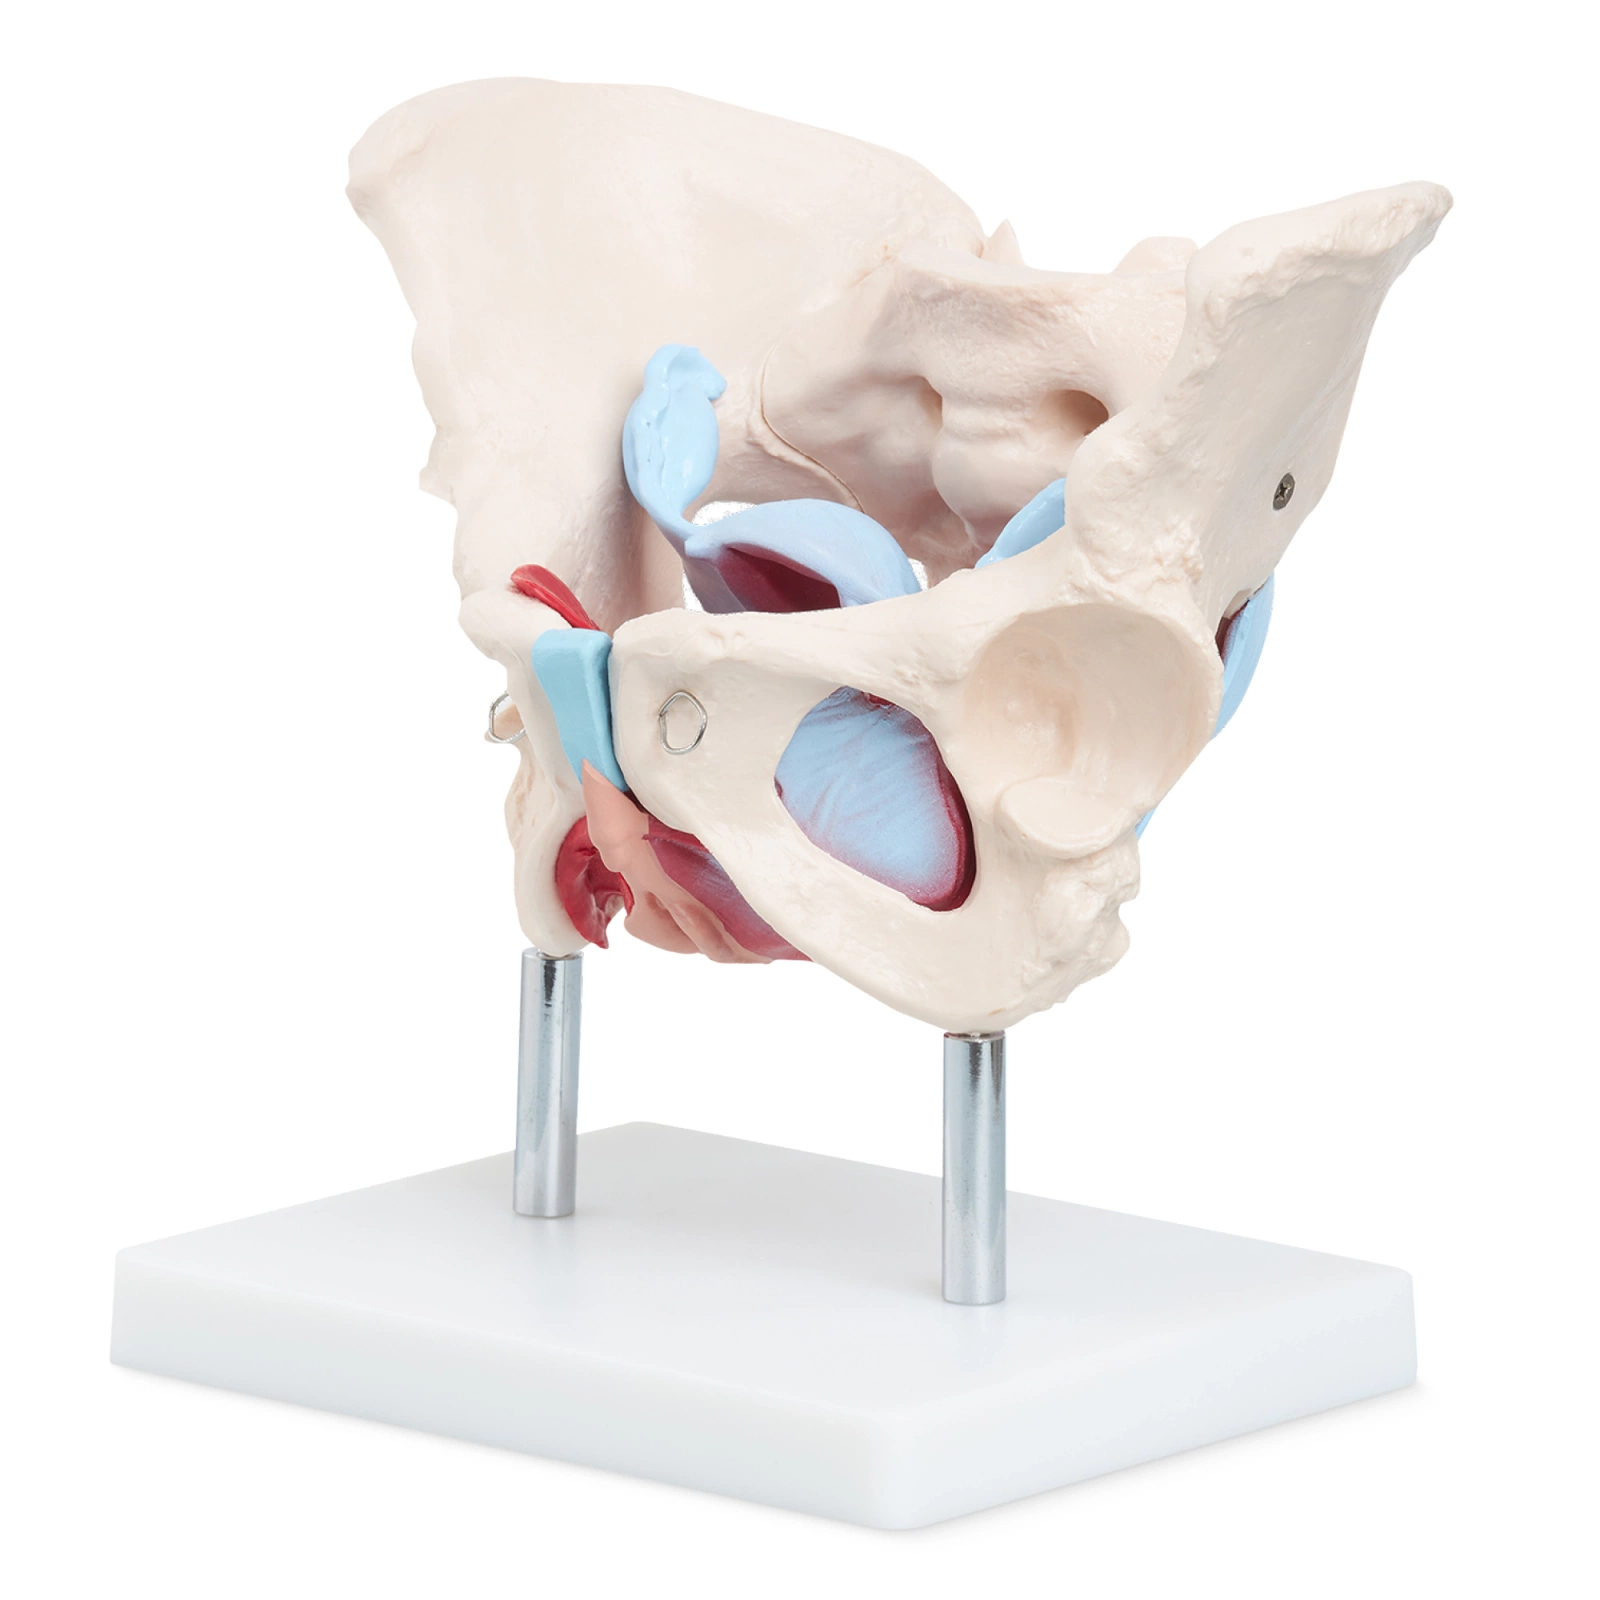

- Wooden Montessori Puzzle on Anatomy: This educational puzzle helps children better understand the human body's structure and develops spatial awareness.